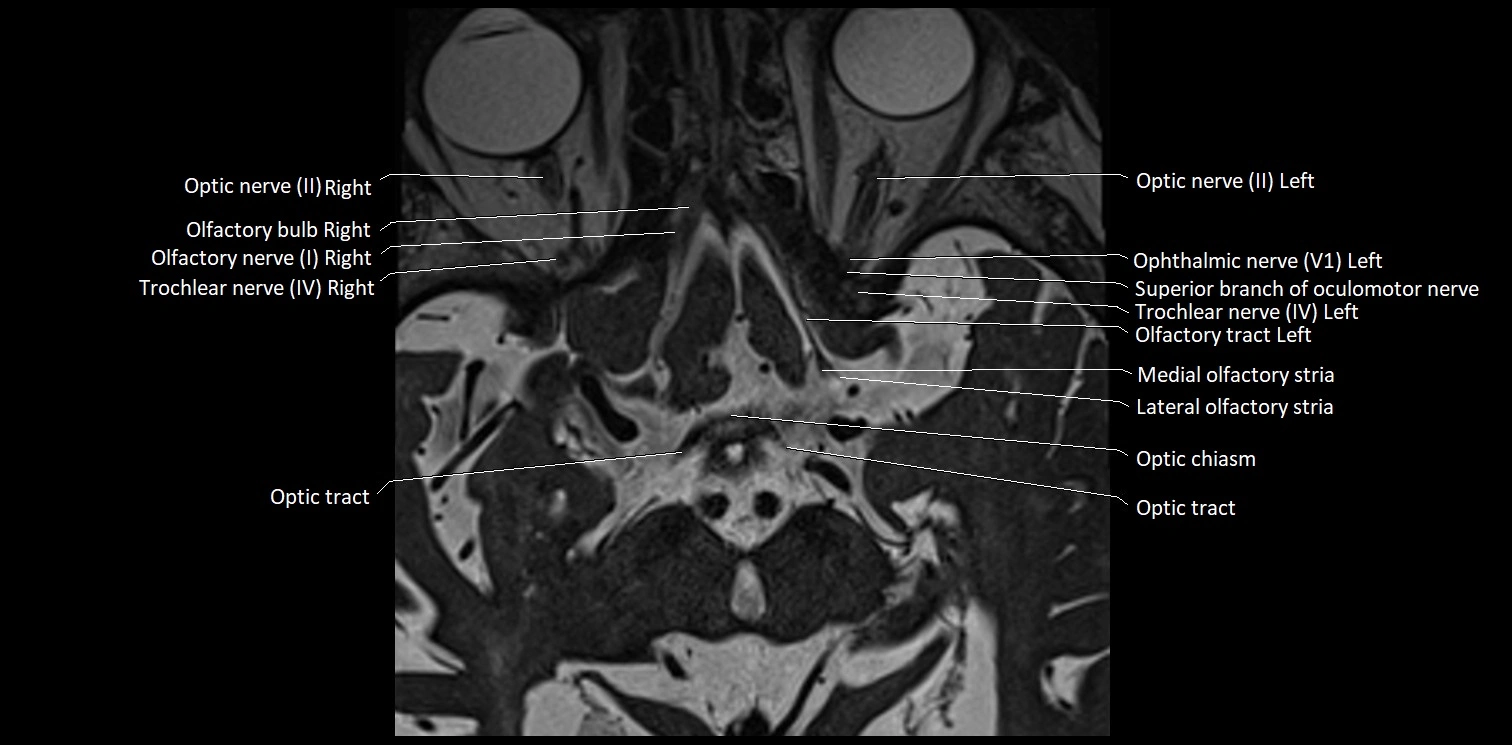

MRI Appearance

• The abducens nerve is a small, thin, linear structure

• Best visualized on high-resolution T2-weighted 3D MRI sequences (e.g., FIESTA or CISS)

• Seen as a hypointense (dark) line running from the brainstem at the pontomedullary junction, traversing the prepontine cistern, and entering Dorello’s canal under the petrosphenoidal ligament, then into the cavernous sinus, and finally the orbit

• May be challenging to visualize in standard MRI due to its small size

• Pathology may be inferred by absence, displacement, or enhancement of the nerve

MRI images

image